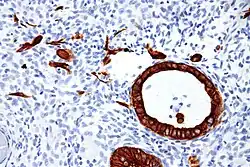

Cytokeratins are keratin proteins found in the intracytoplasmic cytoskeleton of epithelial tissue. They are an important component of intermediate filaments, which help cells resist mechanical stress.[1] Expression of these cytokeratins within epithelial cells is largely specific to particular organs or tissues. Thus they are used clinically to identify the cell of origin of various human tumors.

Expression of these cytokeratins is largely organ or tissue specific. The subsets of cytokeratins which an epithelial cell expresses depends mainly on the type of epithelium, the moment in the course of terminal differentiation and the stage of development. Thus a specific cytokeratin expression profile allows the identification of epithelial cells. Furthermore, this applies also to the malignant counterparts of the epithelia, (carcinomas), as the cytokeratin profile is generally retained. Thus the study of cytokeratin expression by immunohistochemistry techniques is a tool of immense value widely used for tumor diagnosis and characterization in surgical pathology.[5]